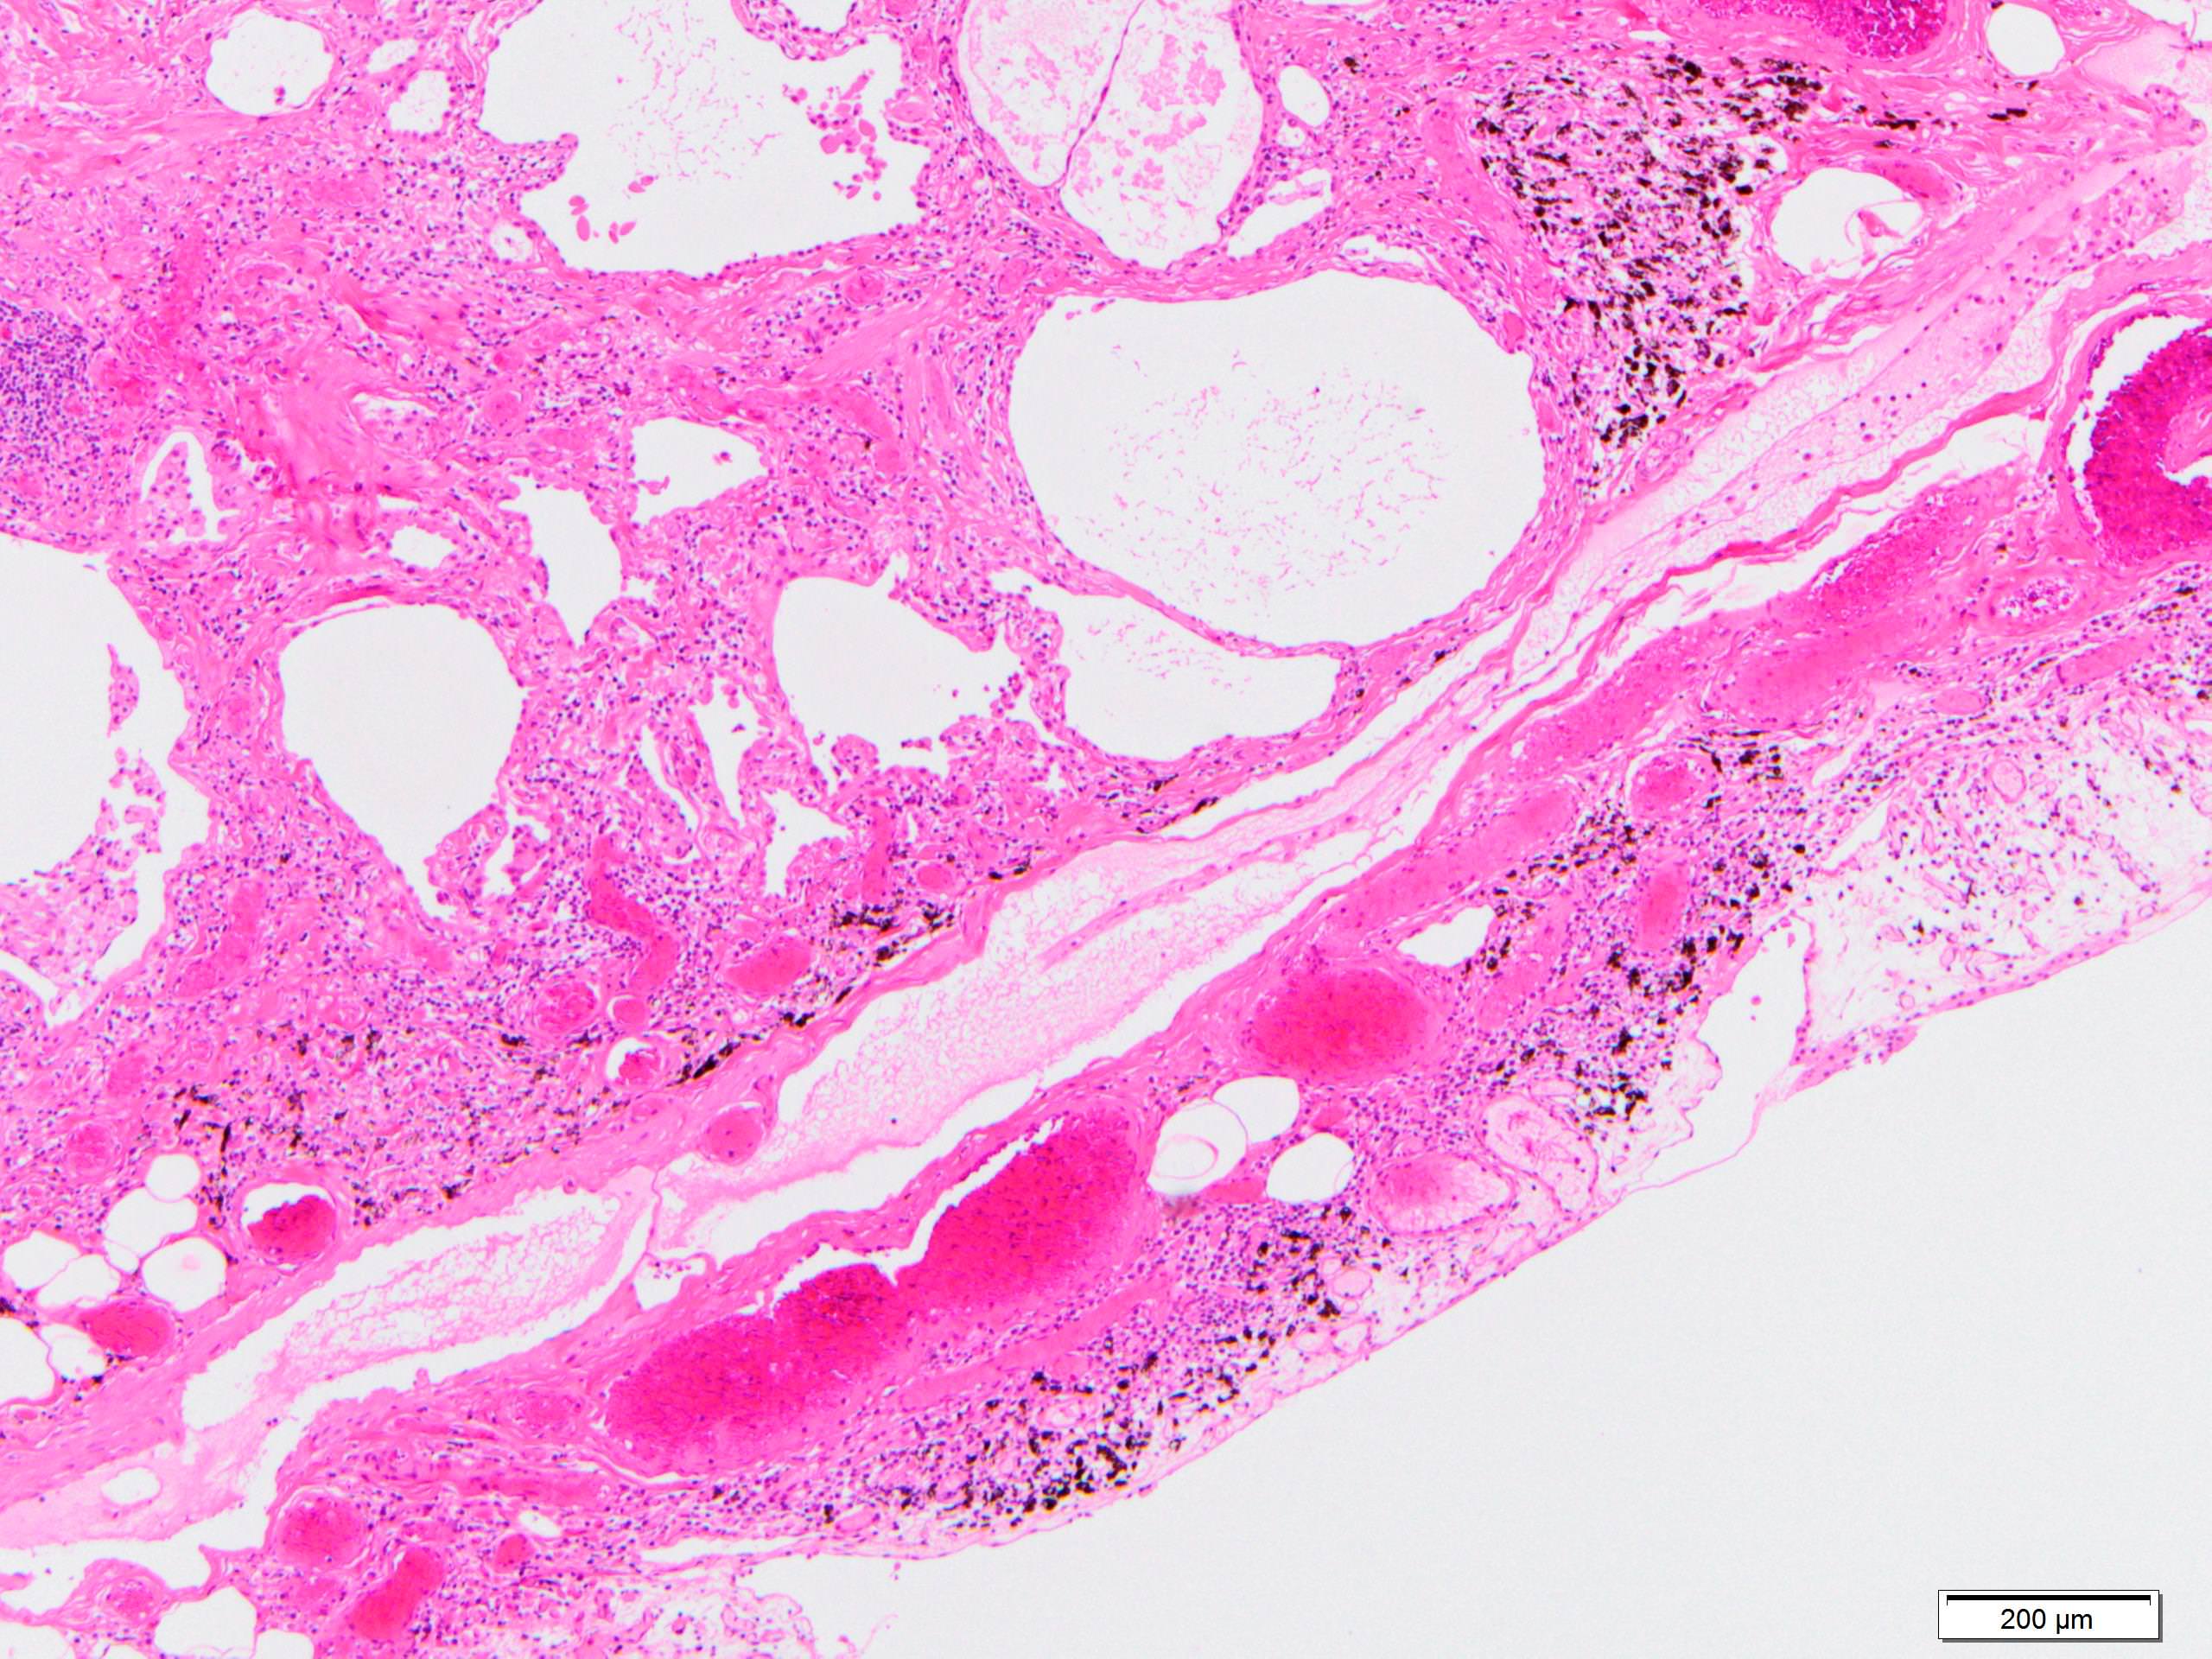

Microscopic (histologic) images

Scroll to see all images.

Contributed by Akira Yoshikawa, M.D.

Gross description

- Diffuse involvement with mild to moderate increase in lung weight

- Fibrotic changes in lower lobes

- Homogeneous and diffuse compared to UIP

- Shrunken lung

- Traction bronchiectasis can be seen

- Honeycomb change can be seen but limited

- Features of interstitial pneumonia with autoimmune features (IPAF) (Chest 2010;138:251):

- Lymphoid aggregates with germinal center

- Extensive pleuritis

- Prominent plasmacytic infiltration

- Dense perivascular collagen

- It is quite rare to see pure NSIP on histology - typically there are focal findings of other interstitial lung disease (Histopathology 2014;65:549)